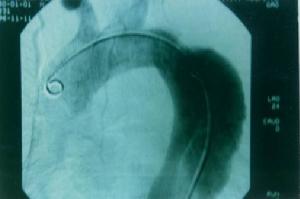

3.心血管異常30%~40%的病人有心血管系統併發症,最常見的心血管異常為主動脈特發性擴張、主動脈夾層動脈瘤和二尖瓣異常等。有時可同時發生主動脈病變和二尖瓣病變。伴有收縮晚期雜音的收縮期喀喇音是其最常見的體徵此外,外傷、高血壓和妊娠可以誘發急性主動脈破裂和夾層動脈瘤形成。除主動脈瓣和二尖瓣病變外,有時尚可發生三尖瓣病變。雖然主動脈擴張總是發生在升主動脈,但胸主動脈和腹主動脈也可發生動脈瘤樣擴張、夾層動脈瘤形成或破裂。約1/3的病人可並有先天性心臟病,常見為主動脈瓣狹窄、動脈導管未閉、房間隔缺損等其他少見的心血管併發症有佛氏竇和肺動脈擴張,主動脈的主要分支如頸總動脈、脾動脈擴張,心內膜纖維變性主動脈瘤破裂和心力衰竭是本綜合徵的主要死亡原因。

(1)主動脈根部明顯增寬,成人主動脈根部內徑男大於35mm,女性大於34mm。

(2)左房/主動脈比率≤0.7。

(3)可同時有二尖瓣脫垂,以後葉多見。

(4)若有主動脈或二尖瓣反流,可出現左室和(或)左房增大。